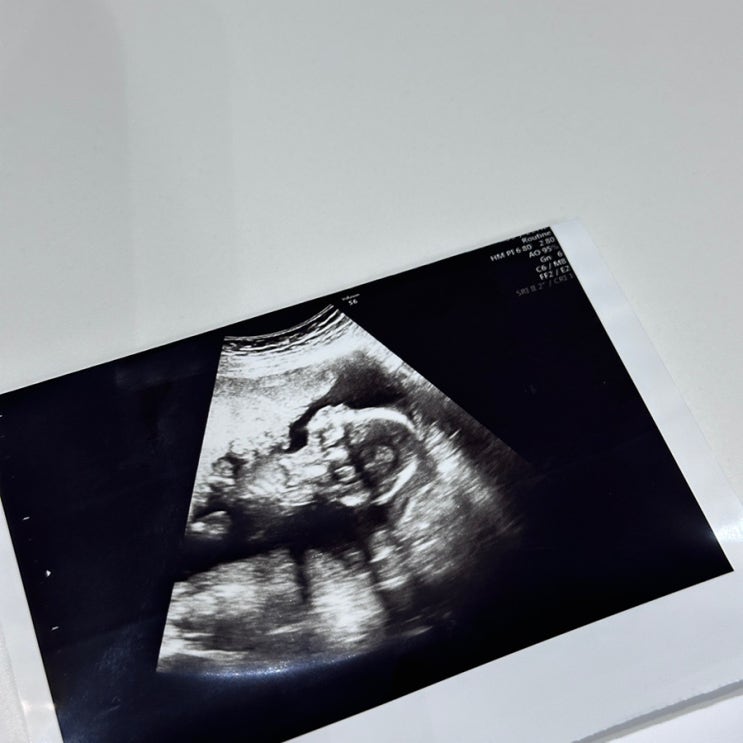

태아 성별 확인 시기 임신 16주 20주 성별 반전 난황 위치별 성별 후기

16주 태아 성별 확인 초음파 후기 태아 성별 확인 시기 임신 16주 20주 성별 반전 난황 위치별 성별 후기 ...